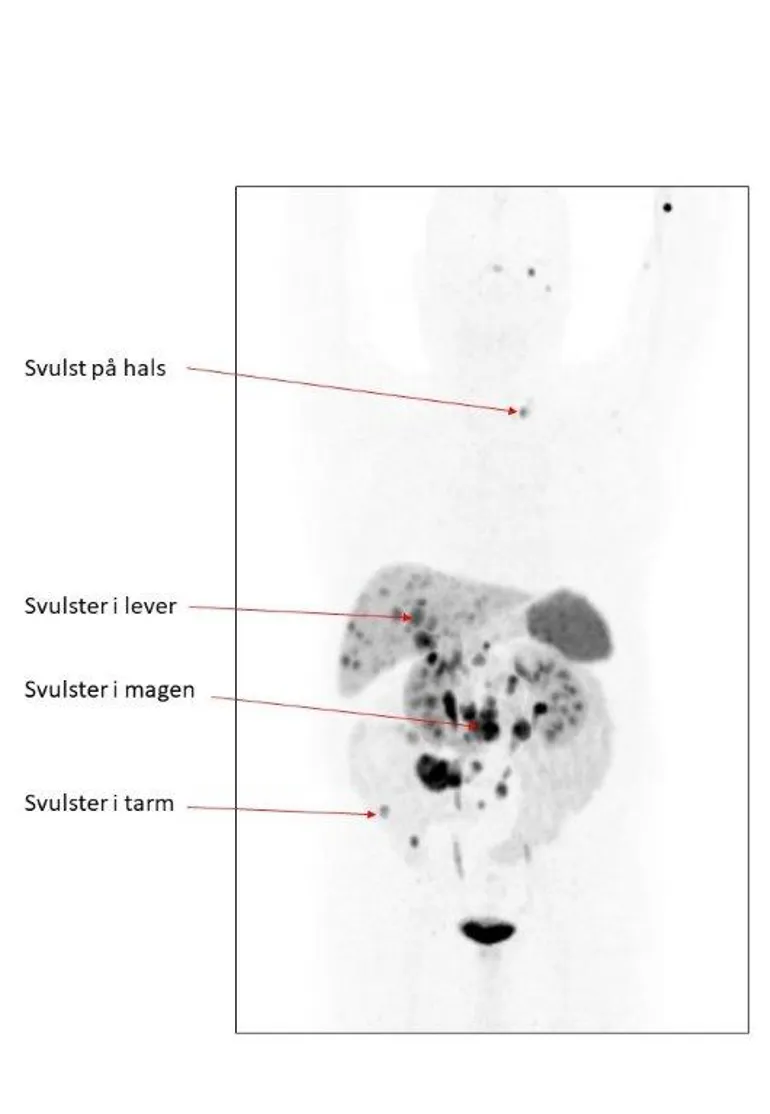

Det er to typer PET «kontrast» som er aktuelle:

- FDG (18FDG-PET). Mest følsom for nevroendokrine carcinomer, mindre eller lite følsom for nevroendokrine svulster.

- Gallium ( 68Gallium-PET). Meget følsom for nevroendokrine svulster. Gjøres for eksempel for å få en eksakt kartlegging av sykdommens utbredelse og vurdere om det er behov for behandling eller endring av behandling.